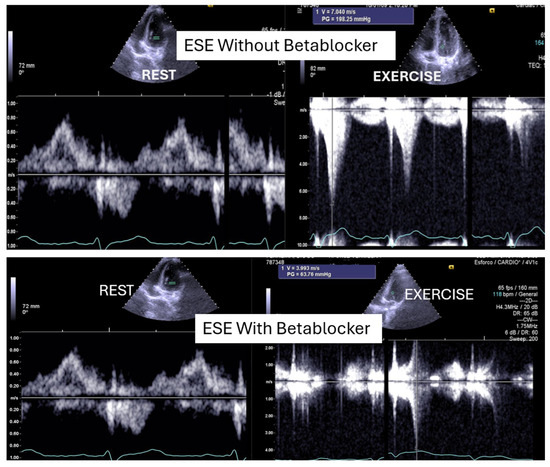

ESE’s potential extends beyond diagnosis, as it may guide targeted therapy. Our experience supports its value in initiating β-blockers in selected pediatric cases (Figure 1 and Figure 2) [1,9].

Figure 1.

This figure shows an intraventricular gradient during exercise in an adolescent experiencing exercise-related chest pain and syncope, accompanied by elevated troponin levels (top). A significant reduction in the gradient is observed under beta-blocker therapy (bottom).

On the resting echocardiogram, all the exams were considered normal with and without beta-blockers. No wall motion abnormalities were detected in any of the exams, with or without beta-blockers. In the complete group, IVPG (Figure 1) at peak exercise on the first assessment was 105 ± 38 mmHg, with mitral valve SAM in 28 adolescents (Figure 2). Among the 29 adolescents treated with beta-blockers, IVPG was 58 ± 32 mmHg, p < 0.0001.

In our study, beta-blocker therapy was associated with reductions in heart rate, exercise-induced ST-segment alterations, systolic blood pressure, and, consequently, peak heart rate–systolic blood pressure product (HR × SBP). The incidence of intraventricular gradients (IVGs) (Figure 1) and systolic anterior motion (SAM) of the mitral valve (Figure 2) during exertion also decreased significantly. These hemodynamic improvements were accompanied by a notable reduction in symptoms during exercise testing and follow-up